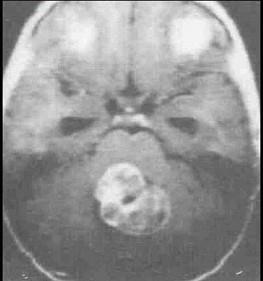

问题 下面哪一项不符合髓母细胞瘤(如图所示)表现()

选项 A.髓母细胞瘤起源于后髓帆外颗粒层的残余胚细胞 B.好发于小脑蚓部 C.主要发生于小儿,是儿童第2位常见肿瘤 D.病情发展较快,一般为半年至1年 E.对放疗不敏感

答案 E